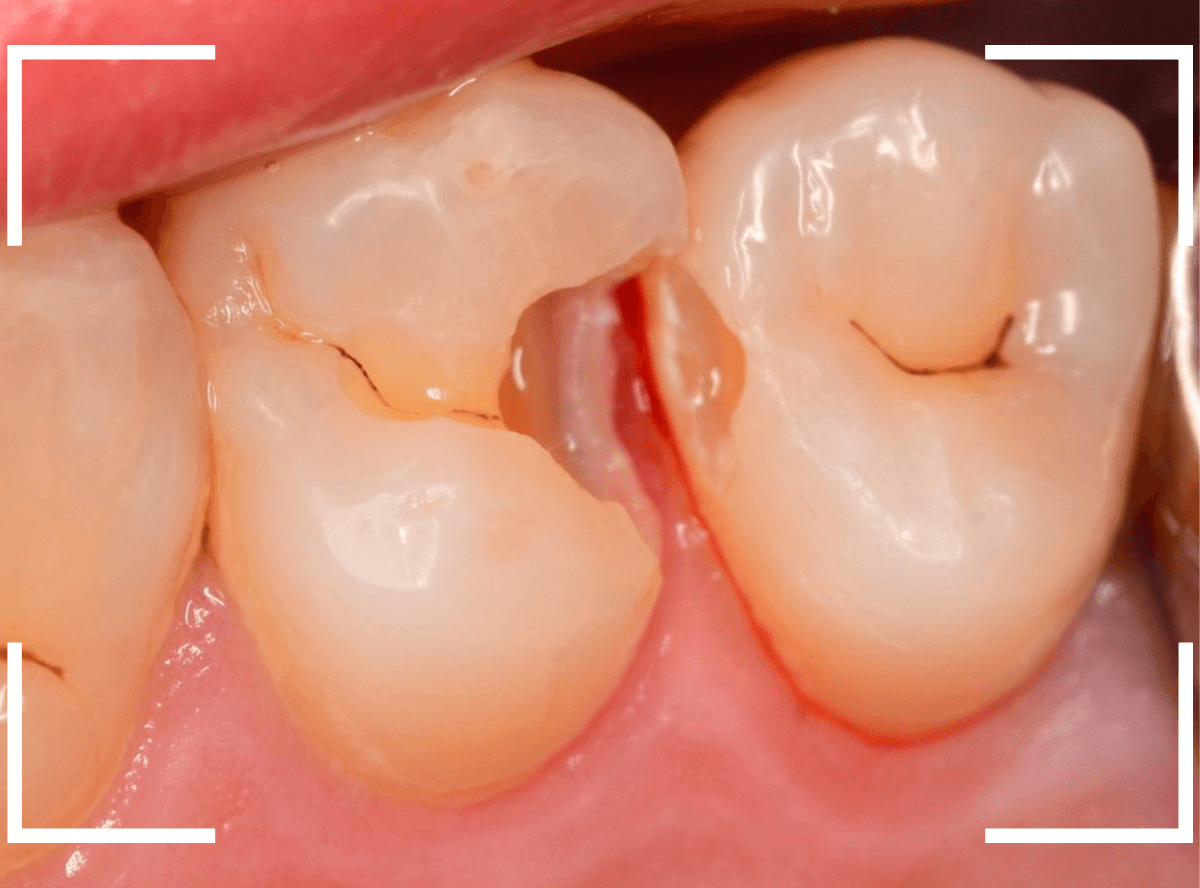

Case.7 歯の側面が大きく虫歯になっていたケース

今回も、歯が欠けたという事で来院された患者さんです。

欠けている部分は小さいですが、歯の側面に大きなつめもの(レジン)が入っています。

一目見て、中で大きな虫歯になっていそうな予感がしました。

レジンのすき間から虫歯が大きく広がってしまっていたようです。

一部、歯肉の中まで虫歯が広がっていました。

歯の側面全体に大きく渡る虫歯でした。